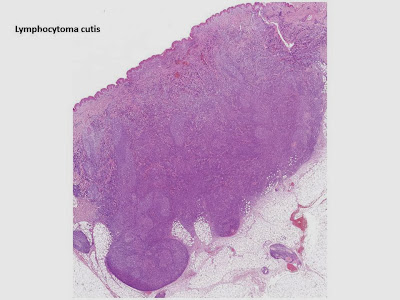

Pseudolymphomas

These are lesions characterised histologically by infiltrates of lymphocytes of mixed lineage ie T and B cells often with associated eosinophils. They are most commonly seen after insect bite reactions. They may show lymph follicle formation.